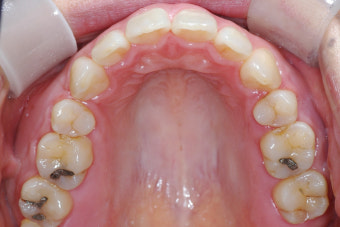

2. 정기 검진과 관리가 꼭 필요한 이유

- 임플란트·틀니는 3~6개월마다 정기 검진 필수. 초기 3개월은 적응 기간.

- 자연 치아 vs 임플란트: 자연 치아는 완충 역할을 하는 치주 인대가 있으나, 임플란트는 없어 합병증 발생 위험↑.

- 합병증(나사 풀림, 파절 등)은 초기 자각 어려움 → 정기 검진 필수.

- 조기 검진은 작은 문제도 빠르게 발견 → 큰 문제 예방 가능.

- 최소 6개월마다 구강 검진 권장 → 큰 증상 없어도 예방 차원 중요.